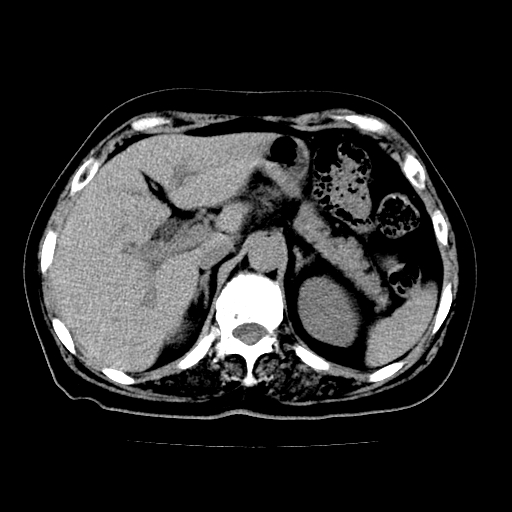

以下是引用lujiandong在2009-2-8 9:37:00的发言:[br]从所发的ct平扫图象上看,胆总管明显增粗,从上向下逐渐变细,是否有泥沙样结石,建议薄层重建;胰腺形态基本正常,左侧肾前筋膜轻度增厚。可以考虑:轻度单纯性胰腺炎,建议ct增强扫描。